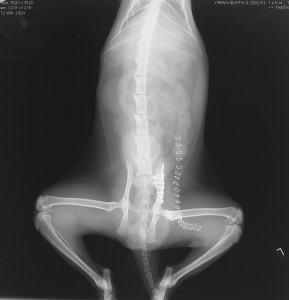

上腕骨粉砕骨折 脛骨近位骨折

骨盤骨折